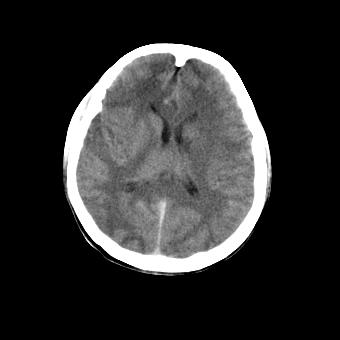

标题: CT16478:男 头晕 恶心 呕吐 [打印本页]

标题: CT16478:男 头晕 恶心 呕吐

病人不合作,图像质量差,右额叶及后纵裂可见高密度影,建议复查。

1.额叶显示密度不均匀,且右侧内见小片稍高密度影, 图像效果差些,不好定?

2.纵裂密度增高,部分脑回密度似乎也增高,蛛网膜下腔出血。

右额叶小片状高密度灶,周围有水肿带,为脑出血;是否有外伤史?若没有,则考虑肿瘤——胶质瘤出血可能性大。

右额叶片状低密度灶,其前内侧小片状略高密度,首先考虑胶质瘤

[quote]以下是引用叶子123在2008-11-13 9:55:00的发言:[br]患者因煤气中毒入院,临床及ct均诊断一氧化碳中毒性脑病[br][br]